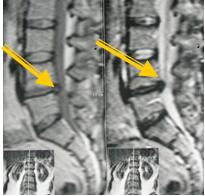

2 стадия — экструзия — выбухание в позвоночный канал элементов фиброзного кольца и дегенерированного пульпозного ядра;

— пролaпс — выпадение в позвоночный канал через дефекты фиброзного кольца фрагментов дегенерированного пульпозного ядра, сохраняющих связь с диском;

Экструзия (трансанулярная) с разрывом продольной связки:

3 стадия — секвестрация — смещение по позвоночному каналу;